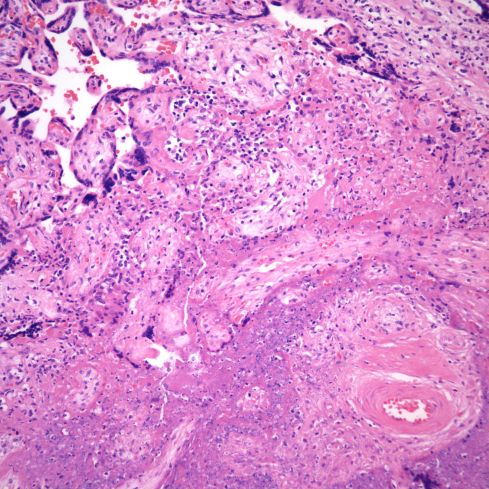

VUE is not restricted to terminal and intermediate villi, but can appear in larger stem villi (Fig 22,23).

Fig 22) There is chronic, somewhat granulomatous inflammation in this stem villus that appears primarily vasocentric with loss of the media seen well in the lower portion of the field between the arrows. The blood in the lumen demonstrates some basophilia and repair around the margins suggestive of vascular stasis. (H&E, 20x)

Fig 23) This is another example of a stem villus with vasocentric as well as subsyncytial inflammation. Note that the vascular inflammation is in the region of the subsyncytial inflammation. There is early lumenal fibrin deposition (arrow).